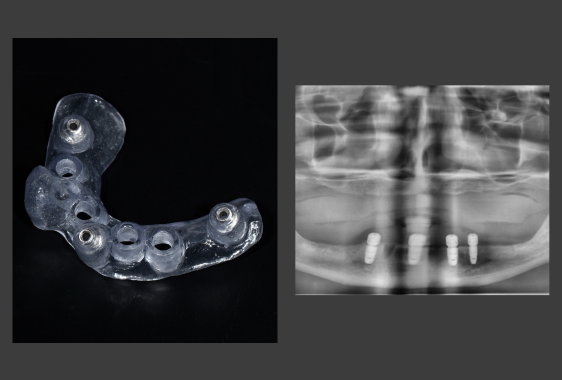

Хірургічний шаблон являє собою персоналізовану 3D-навігаційна капу з отворами для імплантів. Він виготовляється персонально під пацієнта та фіксується в ротовій порожнині протягом імплантації. Трафарет задає точний вектор, глибину, кут нахилу імпланту, забезпечуючи йому довгострокову стабільність і функціональність.

При імплантації без шаблону хірург орієнтується на клінічні маркери, форму альвеолярного гребеня, тактильні відчуття. За давньої втрати зубів анатомія щелепи змінюється, тому візуальні орієнтири стають нечіткими. Навігаційний шаблон мінімізує похибки та підвищує точність операції. Лікар вкручує імпланти в готові отвори, що гарантує точну відповідність попереднім розрахункам.

- Моделювання виробу. Технік проєктує індивідуальний трафарет, доповнений направляючими отворами.

- 3D-друк. Принтер друкує пластиковий виріб по заданих параметрах.